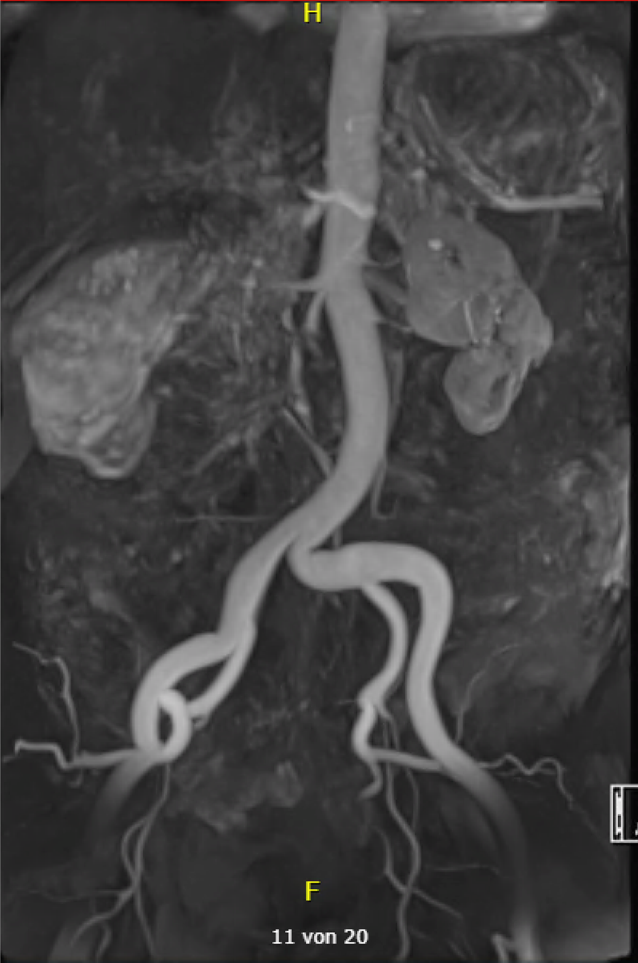

In der Histologie der Lungen- und Lymphknotenbiopsie wurden keine Neoplasien, Granulome oder Hinweise auf eine Castleman-Erkrankung beobachtet, die Befunde waren passend für eine organisierenden Pneumonie. Drei Wochen nach Beginn des Fiebers entwickelte der Patient plötzlich starke Bauchschmerzen, mit klinisch bretthartem Abdomen ohne äußere Blutungsstigmata mit Zeichen eines hämorrhagischen Schocks bei Blutdruckabfall auf systolisch 45 mm Hg, Tachykardie, kalte Peripherie und Anämie (Hb 50 g/l). Eine notfallmäßig durchgeführte abdominale CT-Untersuchung ergab eine perakute abdominale Blutung aus der linken Niere, die sich in das Retroperitoneum und in die Beckenregion ausbreitete (Abb. 2). Zudem wurde ein Verschluss der Arteria lienalis mit nahezu aufgehobener Perfusion der Milz festgestellt und weitere multiple Aneurysmata der abdominalen Arterien (z. B. eines intrapankreatischen Arterienasts und entlang der pankreatikoduodenalen Arkade) im Sinne einer fulminanten generalisierten Arteriopathie. Die konventionelle Notfallangiographie zeigte neben den Aneurysmen der Nierenarterienäste auch mehrere perlschnurartige Gefäßkaliberirregularitäten. Ein rupturiertes Aneurysma/Pseudoaneurysma, das von einem Ast der linken inferioren Nierenarterie ausging, wurde als Ursache der Blutung identifiziert und mittels Coiling des aneurysmatragenden Nierenarterienasts ausgeschaltet. Die Blutung konnte so gestoppt werden (Abb. 2). In Zusammenschau der Befunde stellten wir die Diagnose einer Polyarteriitis nodosa mit einer Gefäßruptur, intraabdominellen Blutung und einem hämorrhagischen Schock. Therapeutisch wurde mit Methylprednisolon intravenös begonnen (500 mg/Tag über 6 Tage). Jedoch kam es bereits am 4. Tag zu einer erneuten arteriellen Blutung, die notfallmäßig mit einem Coiling eines peripheren Asts der A. colica dextra versorgt werden musste (Abb. 3). Angiographisch demarkierten sich weitere Aneurysmen und perlschnurartige Gefäßkaliberirregularitäten der abdominellen Arterien z. B. im Leber- und Nierenhilus links und in der pankreatikoduodenalen Arkade. Nach klinischer Stabilisierung erfolgte eine Umstellung auf Prednison 1 mg/kg Körpergewicht und zusätzlich der Beginn mit Cyclophosphamid. Hierunter wurde ein Rückgang des CRP und der BSR festgestellt. Der Patient erhielt insgesamt 12 (monatliche) Cyclophosphamid-Infusionen (Kumulativdosis 11,6 g), während Prednison auf 5 mg täglich reduziert wurde, was zu einer partiellen Remission der Polyarteriitis nodosa führte. Ein Mangel an Adenosin-Deaminase Typ 2 wurde nicht festgestellt. Danach wurde eine Behandlung mit Tocilizumab 8 mg/kg Körpergewicht intravenös alle 4 Wochen begonnen, die zu einer vollständigen Remission führte und das Absetzen von Prednison ermöglichte. Hierunter zeigte sich in der MRT-Angiographie ein vollständiges Verschwinden der Aneurysmata und Pseudoaneurysmata innerhalb der gastrointestinalen und renalen Arterien (Abb. 4).

Abb. 2

ab Abdominelle CT-Angiographie in arterieller Phase. cd DSA-Angiographie im Rahmen des notfallmäßigen Coilings eines Nierenarterienasts links bei rupturiertem Aneurysma/Pseudoaneurysma mit hämodynamisch relevanter retroperitonealer Blutung. Multiple Aneurysmata abdomineller Arterienäste, z. B. der intrarenalen Nierenarterienäste bds. und eines intrapankreatischen Arterienasts (d Pfeil), zudem fallen deutlich die perlschnurartigen Gefäßkaliberirregularitäten der intrarenalen Nierenarterienäste auf